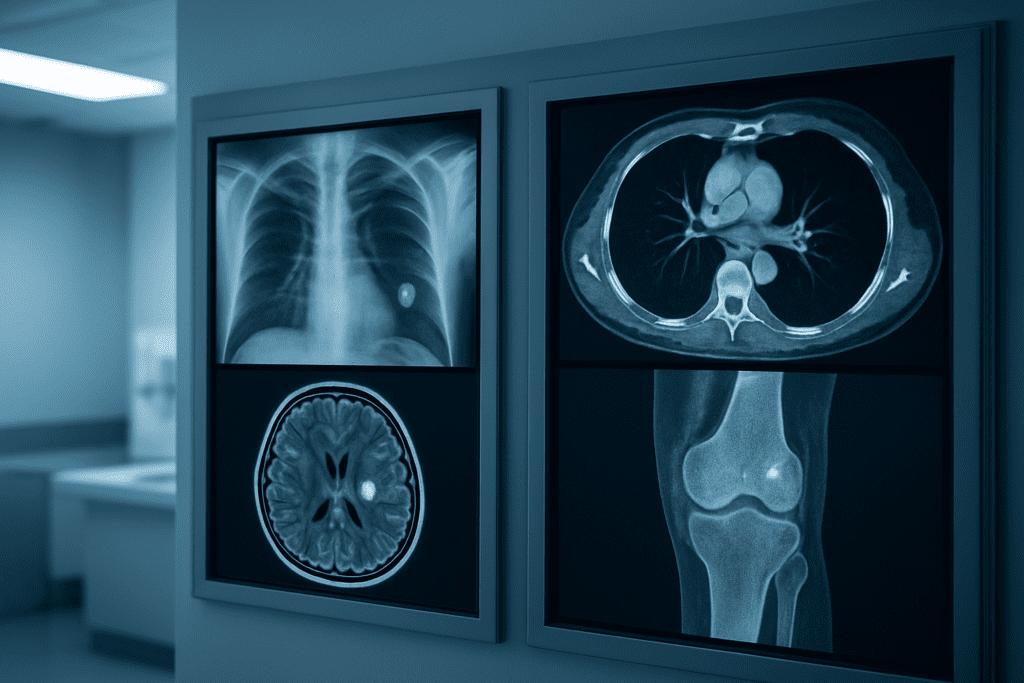

Essential Medical Imaging Technologies for Early Disease Detection

X-ray screenings for bone health and lung condition assessment

Chest X-rays remain the most accessible screening tool for detecting lung abnormalities, including early-stage tumors, infections, and chronic obstructive pulmonary disease before symptoms develop. Bone density scans using dual-energy X-ray absorptiometry (DEXA) effectively identify osteoporosis risk, enabling preventive treatment that reduces fracture likelihood by up to 70%.

Standard radiographs can reveal joint deterioration, spinal compression fractures, and subtle lung nodules that might indicate cancer development. Regular screening intervals vary based on age and risk factors, with annual chest X-rays recommended for high-risk patients and bone density testing every two years for postmenopausal women.

CT scans for comprehensive organ evaluation

Low-dose computed tomography screening excels at detecting lung cancer in high-risk smokers, reducing mortality by 20% when performed annually. Coronary artery calcium scoring through cardiac CT provides precise cardiovascular risk assessment, identifying atherosclerosis decades before heart attacks occur.

Abdominal CT scans can reveal kidney stones, liver abnormalities, pancreatic masses, and early-stage colorectal polyps during routine health evaluations. Virtual colonoscopy using CT technology offers a non-invasive alternative to traditional colonoscopy, detecting polyps larger than 6mm with 90% accuracy.

MRI advantages in soft tissue and neurological screening

Magnetic resonance imaging provides unparalleled soft tissue contrast without radiation exposure, making it ideal for detecting brain tumors, multiple sclerosis lesions, and spinal cord abnormalities before neurological symptoms appear. Cardiac MRI accurately assesses heart muscle damage and identifies inherited cardiomyopathies that could lead to sudden cardiac death.